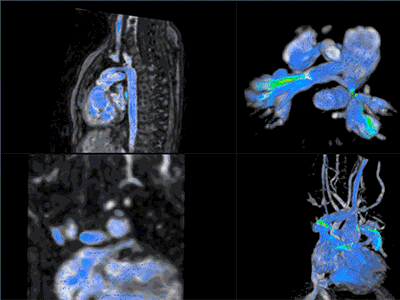

Dr. Kanter specializes in diagnostic and interventional pediatric cardiac catheterization for the treatment of congenital heart disease. He has extensive experience with transcatheter pulmonary valve implantation and is an expert in the device closure of atrial septal defects, ventricular septal defects and patent ductus arteriosus. Dr. Kanter is the site principal investigator on the RO1 grant titled “Cardiac MRI Increases Accuracy and Decreases Risk of Evaluation of Children with Cardiomyopathy and Cardiac Transplantation” funded by the National Heart Lung and Blood Institute of the National Institutes of Health. He has also been an investigator in several national multi-center research studies to examine new interventional devices and to track clinical outcomes.